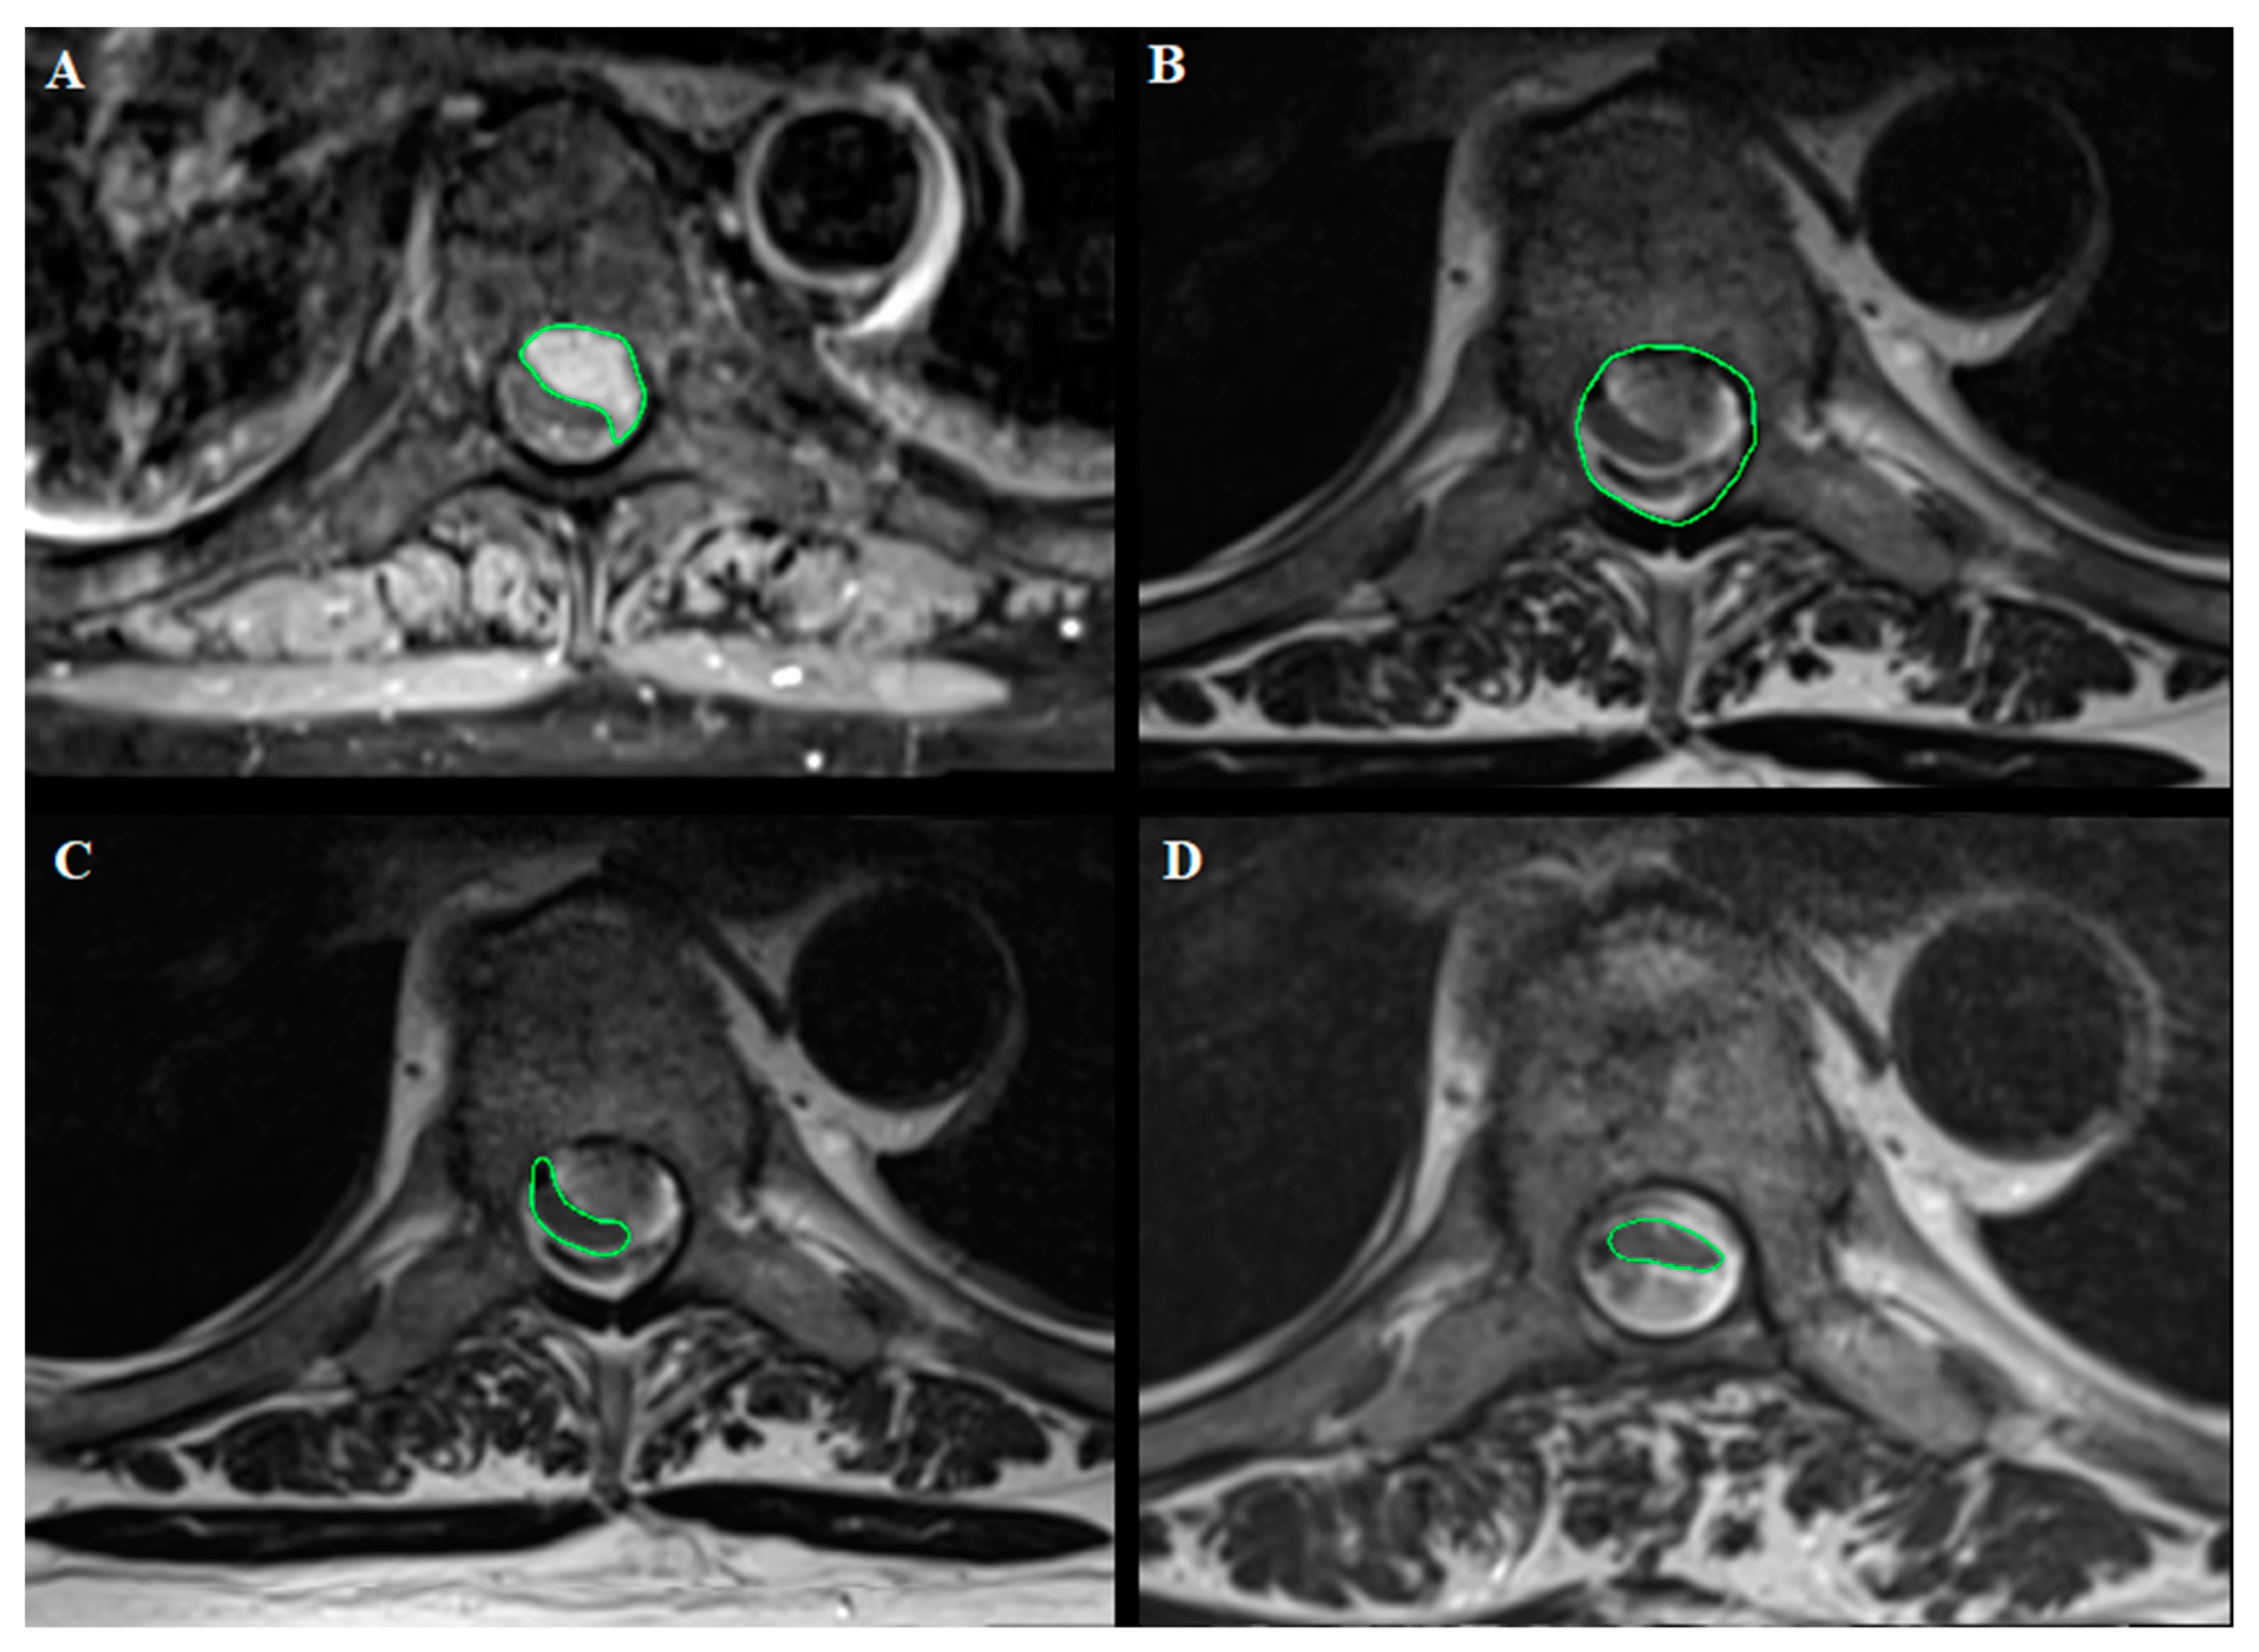

- Areas (mm2) related to tumor and cord occupancy at maximum compression level and the degree of spinal cord compression, applying the formula reported by Davies et al. [19] and illustrated in Table 1, with the other previous studies reporting SMs volume analysis. The results are reported as % according to the author. This was calculated using OsiriX Lite® software, based on axial T1-weighted images with contrast and axial T2-weighted images (Figure 2).

Figure 2. Dorsal Th7 WHO grade I meningioma with anterior dural attachment: (A) Tumor area (111 mm2) measured at maximal compression on axial T1-weighted images after contrast administration; (B) spinal canal area (210 mm2) measured at maximal compression on axial T2-weighted images; (C) spinal cord area (39 mm2) measured at maximal compression on axial T2-weighted images; (D) postoperative spinal cord area (42 mm2) measured at the level of preoperative maximal compression on axial T2-weighted images. The measurements were made using OsiriX Lite®. - The degree of postoperative cord expansion (%) at the level of preoperative maximum compression calculated as above based on axial T2-weighted images.